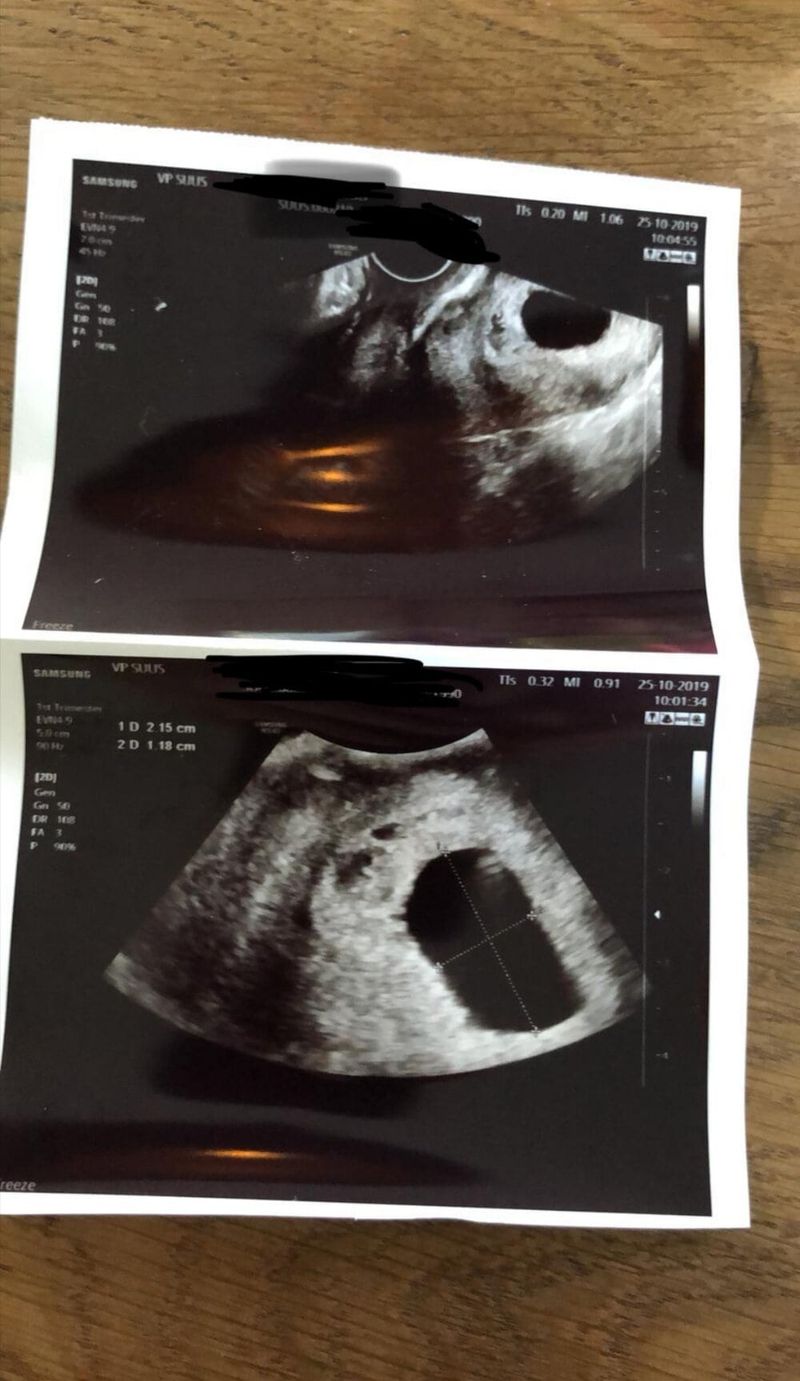

Eén week later was er nog niks gebeurd. Met een klein sprankje hoop reden wij weer naar het ziekenhuis toe. Dit keer werden we te woord gestaan door een andere gynaecoloog. Deze begon gelijk het verhaal over de miskraamopwekkers en de curretage. Na haar even haar gang te hebben laten gaan, waren we het zat. Er was ons namelijk nog een echo beloofd! Hoe kun je nou over iets beginnen als er toch nog een ietsiepietsie beetje hoop is? Ze vond dit maar raar, maar goed, als wij er op stonden dan deden we dat maar. Nouja zeg! Helaas was er nog geen vruchtje te zien, zoals verwacht. Maar toch blijf je natuurlijk iets hoop houden. Na nog een geïrriteerd gesprek, hebben we besloten om voor de medicatie te kiezen. Ze zeiden dat een curretage gewoon meer risico´s (op beschadiging en dergelijke) met zich mee zou brengen, dus vandaar onze keuze.

Ruim één week na de medicatie was de check echo, om te zien of alles was gelukt. Hier hebben wij gelijk aangegeven dat wij de vorige gynaecoloog echt niet konden waarderen. Dit keer had ik (weer een andere) meneer die erg lief en meelevend was. Helaas was er op de echo nog het gehele vruchtzakje te zien die zelfs nog meegegroeid was, net als ik! Hij vond het maar raar dat de vorige gynaecoloog maar één kuur had meegegeven. Van hem kreeg ik een abortus pil (die moest ik de avond voor de kuur innemen) en een dubbele kuur, dus acht tabletten mee. Ook hiervoor hebben wij weer het weekend uitgekozen zodat onze dochter uit logeren kon. Twee dagen lang heb ik weer met een matje op de bank gelegen. Dit keer kwam er echter nog minder uit als die keer ervoor. Ik zag de bui dus alweer hangen en had al het gevoel dat ik alsnog een curretage moest ondergaan.

Ruim een week later mochten wij weer voor een echo komen. Weer hadden wij een andere gynaecoloog die de echo ging maken. Maar… goed nieuws dit keer! Het vruchtzakje was geen 8 centimeter meer, maar was geslonken tot 0,5 millimeter! Wauw, dit hadden wij nooit verwacht! De gynaecoloog melde dat ik waarschijnlijk die maand erop wel weer ongesteld zou worden (deze afspraak was op 18 november), en met deze ongesteldheid zou dit hele kleine restje nog meekomen! Yes, eindelijk! Nu kunnen wij deze miskraam een plekje gaan geven en afsluiten.